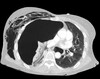

What pathology is seen here?

Bronchiectasis ## Footnote -Airway very dilated -Walls are normal thickness

109

Bronchiectasis ## Footnote -Signet ring appearance (ring is the bronchus, stone sitting on the ring is the blood vessel beside)

110